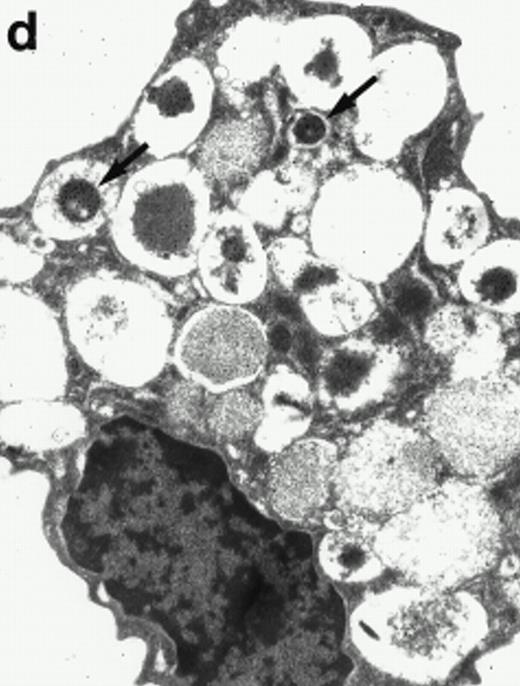

Morphologic analyses of both mature eosinophils and day-24 IL-5–induced UCC by immunoelectron microscopy were performed with proMBP-specific monoclonal antibody (J163-15E10) and with polyclonal antibody to MBP (rabbit #14). No proMBP staining was observed in peripheral blood eosinophils (Fig 6a); in contrast, MBP was localized specifically to the granule crystalline core (Fig 6b). Day-24 IL-5–induced UCC showed marked proMBP labeling of large uncondensed granules and minimal labeling of small condensed granules (Fig 6c); remarkably, proMBP was often seen as a ring around what appeared to be a granule in the process of condensing (black arrow). MBP labeling was confined primarily to condensing granules (Fig6d). Figure 7 shows results from double immunogold labeling of both proMBP (small gold) and MBP (large gold). ProMBP was concentrated in large uncondensed granules, and MBP was concentrated in condensed granules. Some granules (black arrow in Fig7b) contained labeling for MBP (primarily in the center) and proMBP (at the periphery). Controls using either normal mouse immunoglobulin or normal rabbit immunoglobulin as the primary label were negative (results not shown).

Localization of proMBP and MBP by immunoelectron microscopy. (a) A peripheral blood eosinophil labeled with anti-proMBP J163-15E10. Note the absence of specific labeling. (b) A peripheral blood eosinophil labeled with rabbit anti-MBP. Note that MBP is specifically localized to the granule crystalline core (black arrows). (c) Day-24 IL-5–induced UCC labeled with anti-proMBP. The black arrow shows localization of proMBP predominantly to the periphery of a condensing granule; very little proMBP is present in the interior of that granule. The white arrow points to a condensed granule, which lacks proMBP label. Also, note the presence of a large uncondensed granule densely labeled with proMBP proximal to the nucleus (open white arrowhead). (d) Day-24 IL-5–induced UCC labeled with anti-MBP. MBP is localized primarily to the interior of condensing granules (black arrows). (a, c, and d) Original magnification ×11,000; (b) ×15,000.

Localization of proMBP and MBP in day-24 IL-5–induced UCC by immunoelectron microscopy using double labeling. ProMBP was localized with 15-nm colloidal gold particles and MBP with 30-nm gold particles. (a) Although proMBP labeling (small gold) is seen throughout the Golgi, it is concentrated predominantly in the large uncondensed granules (white arrow); only minimal MBP labeling (large gold) is evident in the large granules. In contrast, the small condensed granules show marked MBP labeling in the interior and minimal proMBP labeling at the periphery (black arrow). (b) At higher magnification, dense labeling for proMBP (small gold) and minimal labeling for MBP (large gold) is evident in a large uncondensed granule (white arrow). The black arrow identifies a small condensed granule that contains predominantly MBP, along with minimal proMBP at the periphery. (a) Original magnification ×11,000; (b) ×20,000.